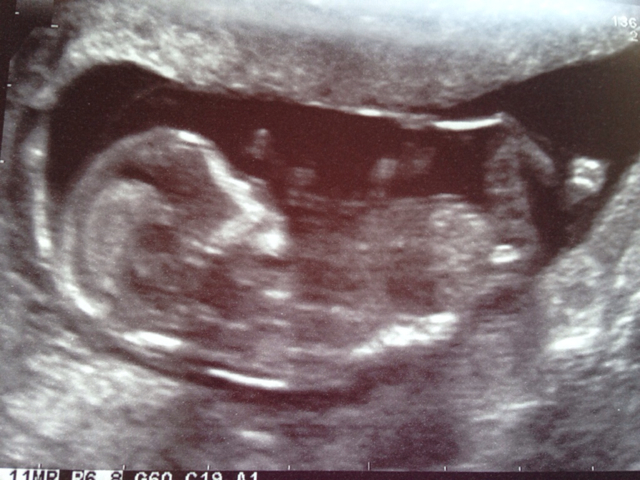

I can't see any clues sorry

No nub. Love the feet!

I can't see the nub.

Any skull guessers?

Skull looks girly!

maybe girl